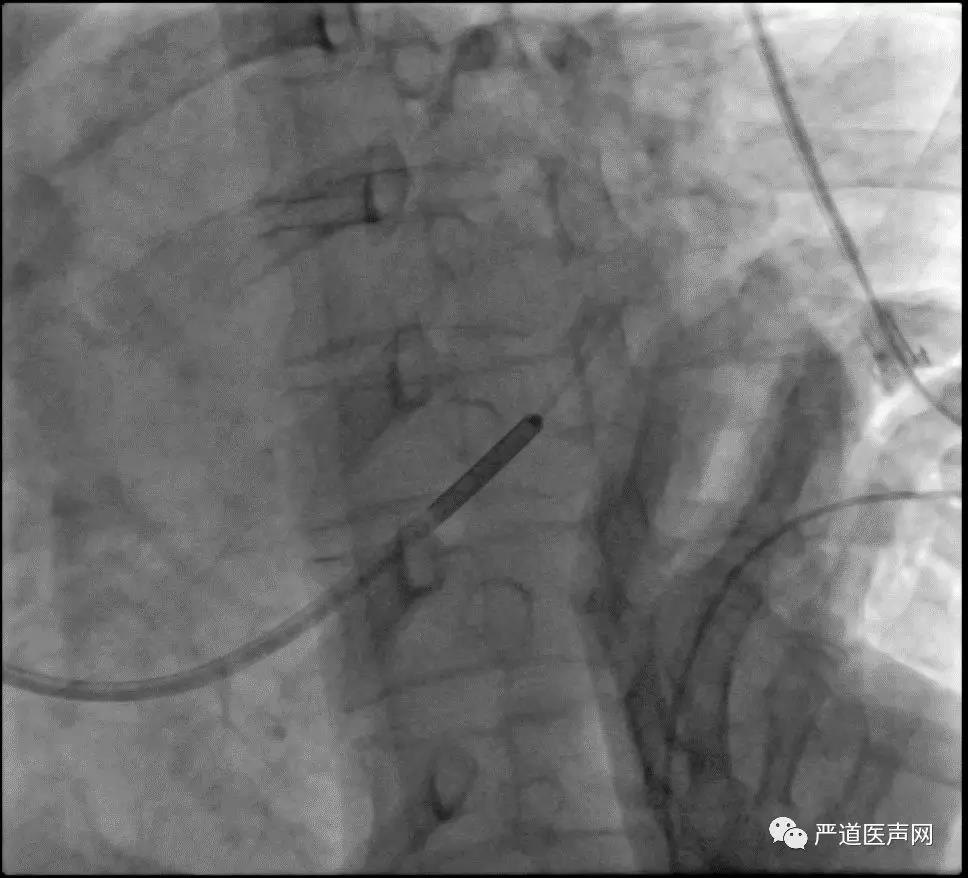

11.jpg

12.jpg

鞘中鞘靶血管造影